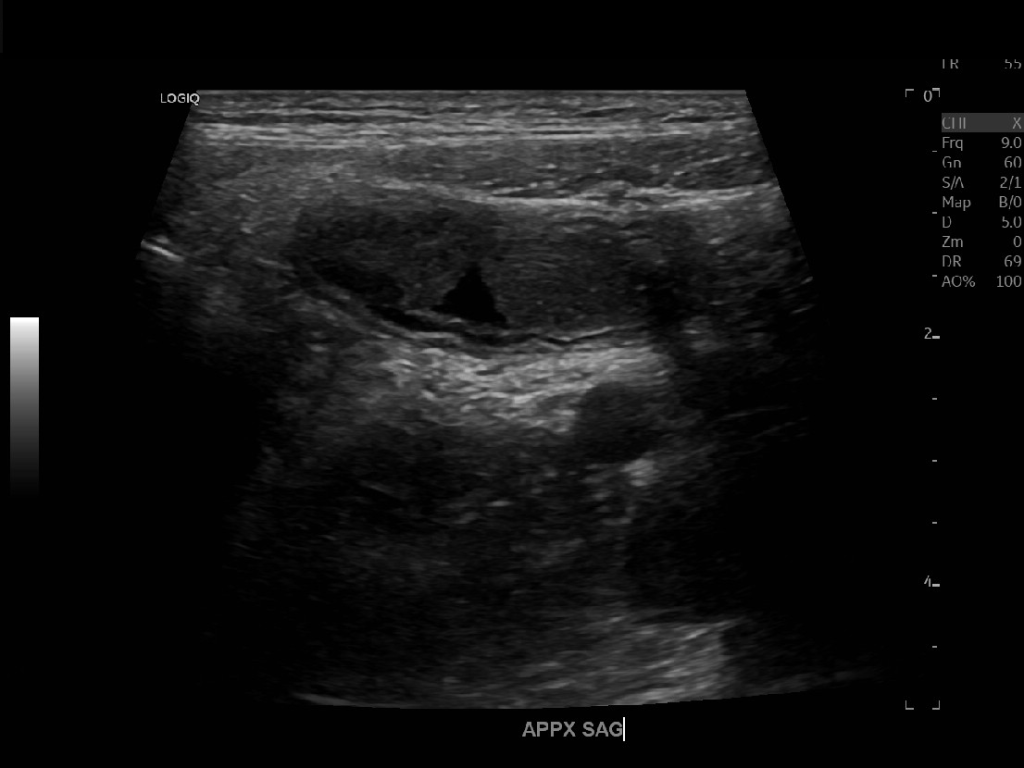

Appendicitis 13

Acute appendicitis @ 1 cm with L2-9mhz and L6-24mhz transducer GE Logiq e10.